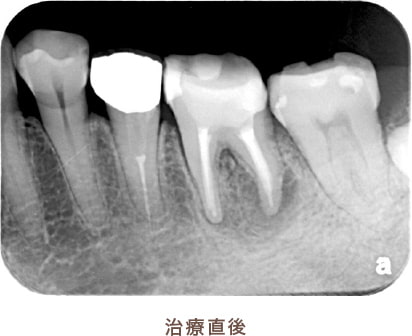

治療後病気がなくなり骨が再生した